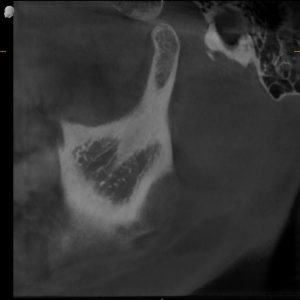

MRI confirmed bilateral disc displacement without reduction — both jaw joints had discs that had slipped out of position, causing compression and inflammation.

Clinical & Radiographic Findings

- Bilateral disc displacement without reduction

- Restricted opening (31 mm → improved to 47 mm)

- Myofascial tenderness and deep bite

- Significant parafunctional clenching pattern

Bilateral TMJ dysfunction with disc displacement and muscular hyperactivity.